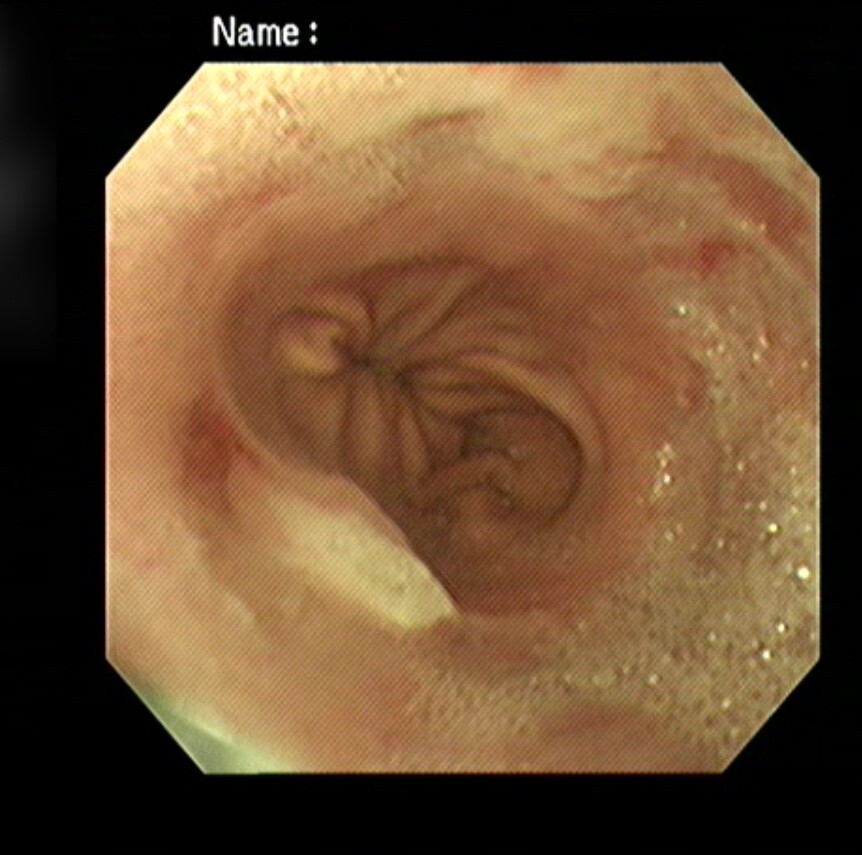

내시경 검사에서는 확장된 식도와

위-식도 연접 부위의 염증,

닫혀있어야 할 위-식도 연결 부위가

열린 상태로 위점막이 식도 내로 돌출되어

있는 것이 확인되었습니다.